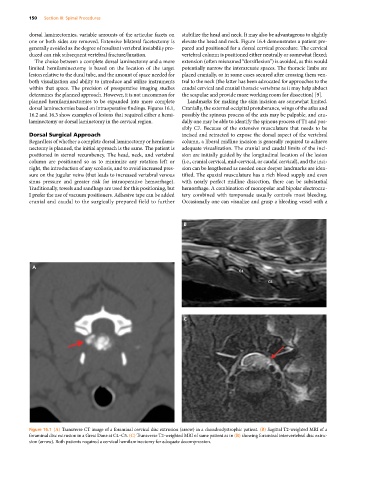

Figure 16.1 (A) Transverse CT image of a foraminal cervical disc extrusion (arrow) in a chondrodystrophic patient. (B) Sagittal T2‐weighted MRI of a

foraminal disc extrusion in a Great Dane at C4–C5. (C) Transverse T2‐weighted MRI of same patient as in (B) showing foraminal intervertebral disc extru-

sion (arrow). Both patients required a cervical hemilaminectomy for adequate decompression.